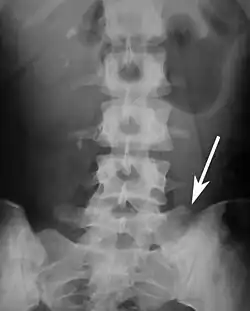

Sacralization of the fifth lumbar vertebra (or sacralization) is a congenital anomaly, in which the transverse process of the last lumbar vertebra (L5) fuses to the sacrum on one side or both, or to ilium, or both. These anomalies are observed in about 3.5 percent of people, and it is usually bilateral but can be unilateral or incomplete (ipsilateral or contralateral rudimentary facets) as well. Although sacralization may be a cause of low back pain, it is asymptomatic in many cases (especially bilateral type). Low back pain in these cases most likely occurs due to biomechanics. In sacralization, the L5-S1 intervertebral disc may be thin and narrow. This abnormality is found by X-ray.

Sacralization of L6 means L6 attaches to S1 via a rudimentary joint. This L6-S1 joint creates additional motion, increasing the potential for motion-related stress and lower back pain/conditions. This condition can usually be treated without surgery, injecting steroid medication at the pseudoarticulation instead. Additionally, if L6 fuses to another vertebra this is increasingly likely to cause lower back pain.[3] The presence of a sixth vertebra in the space where five vertebrae normally reside also decreases the flexibility of the spine and increases the likelihood of injury.[4]